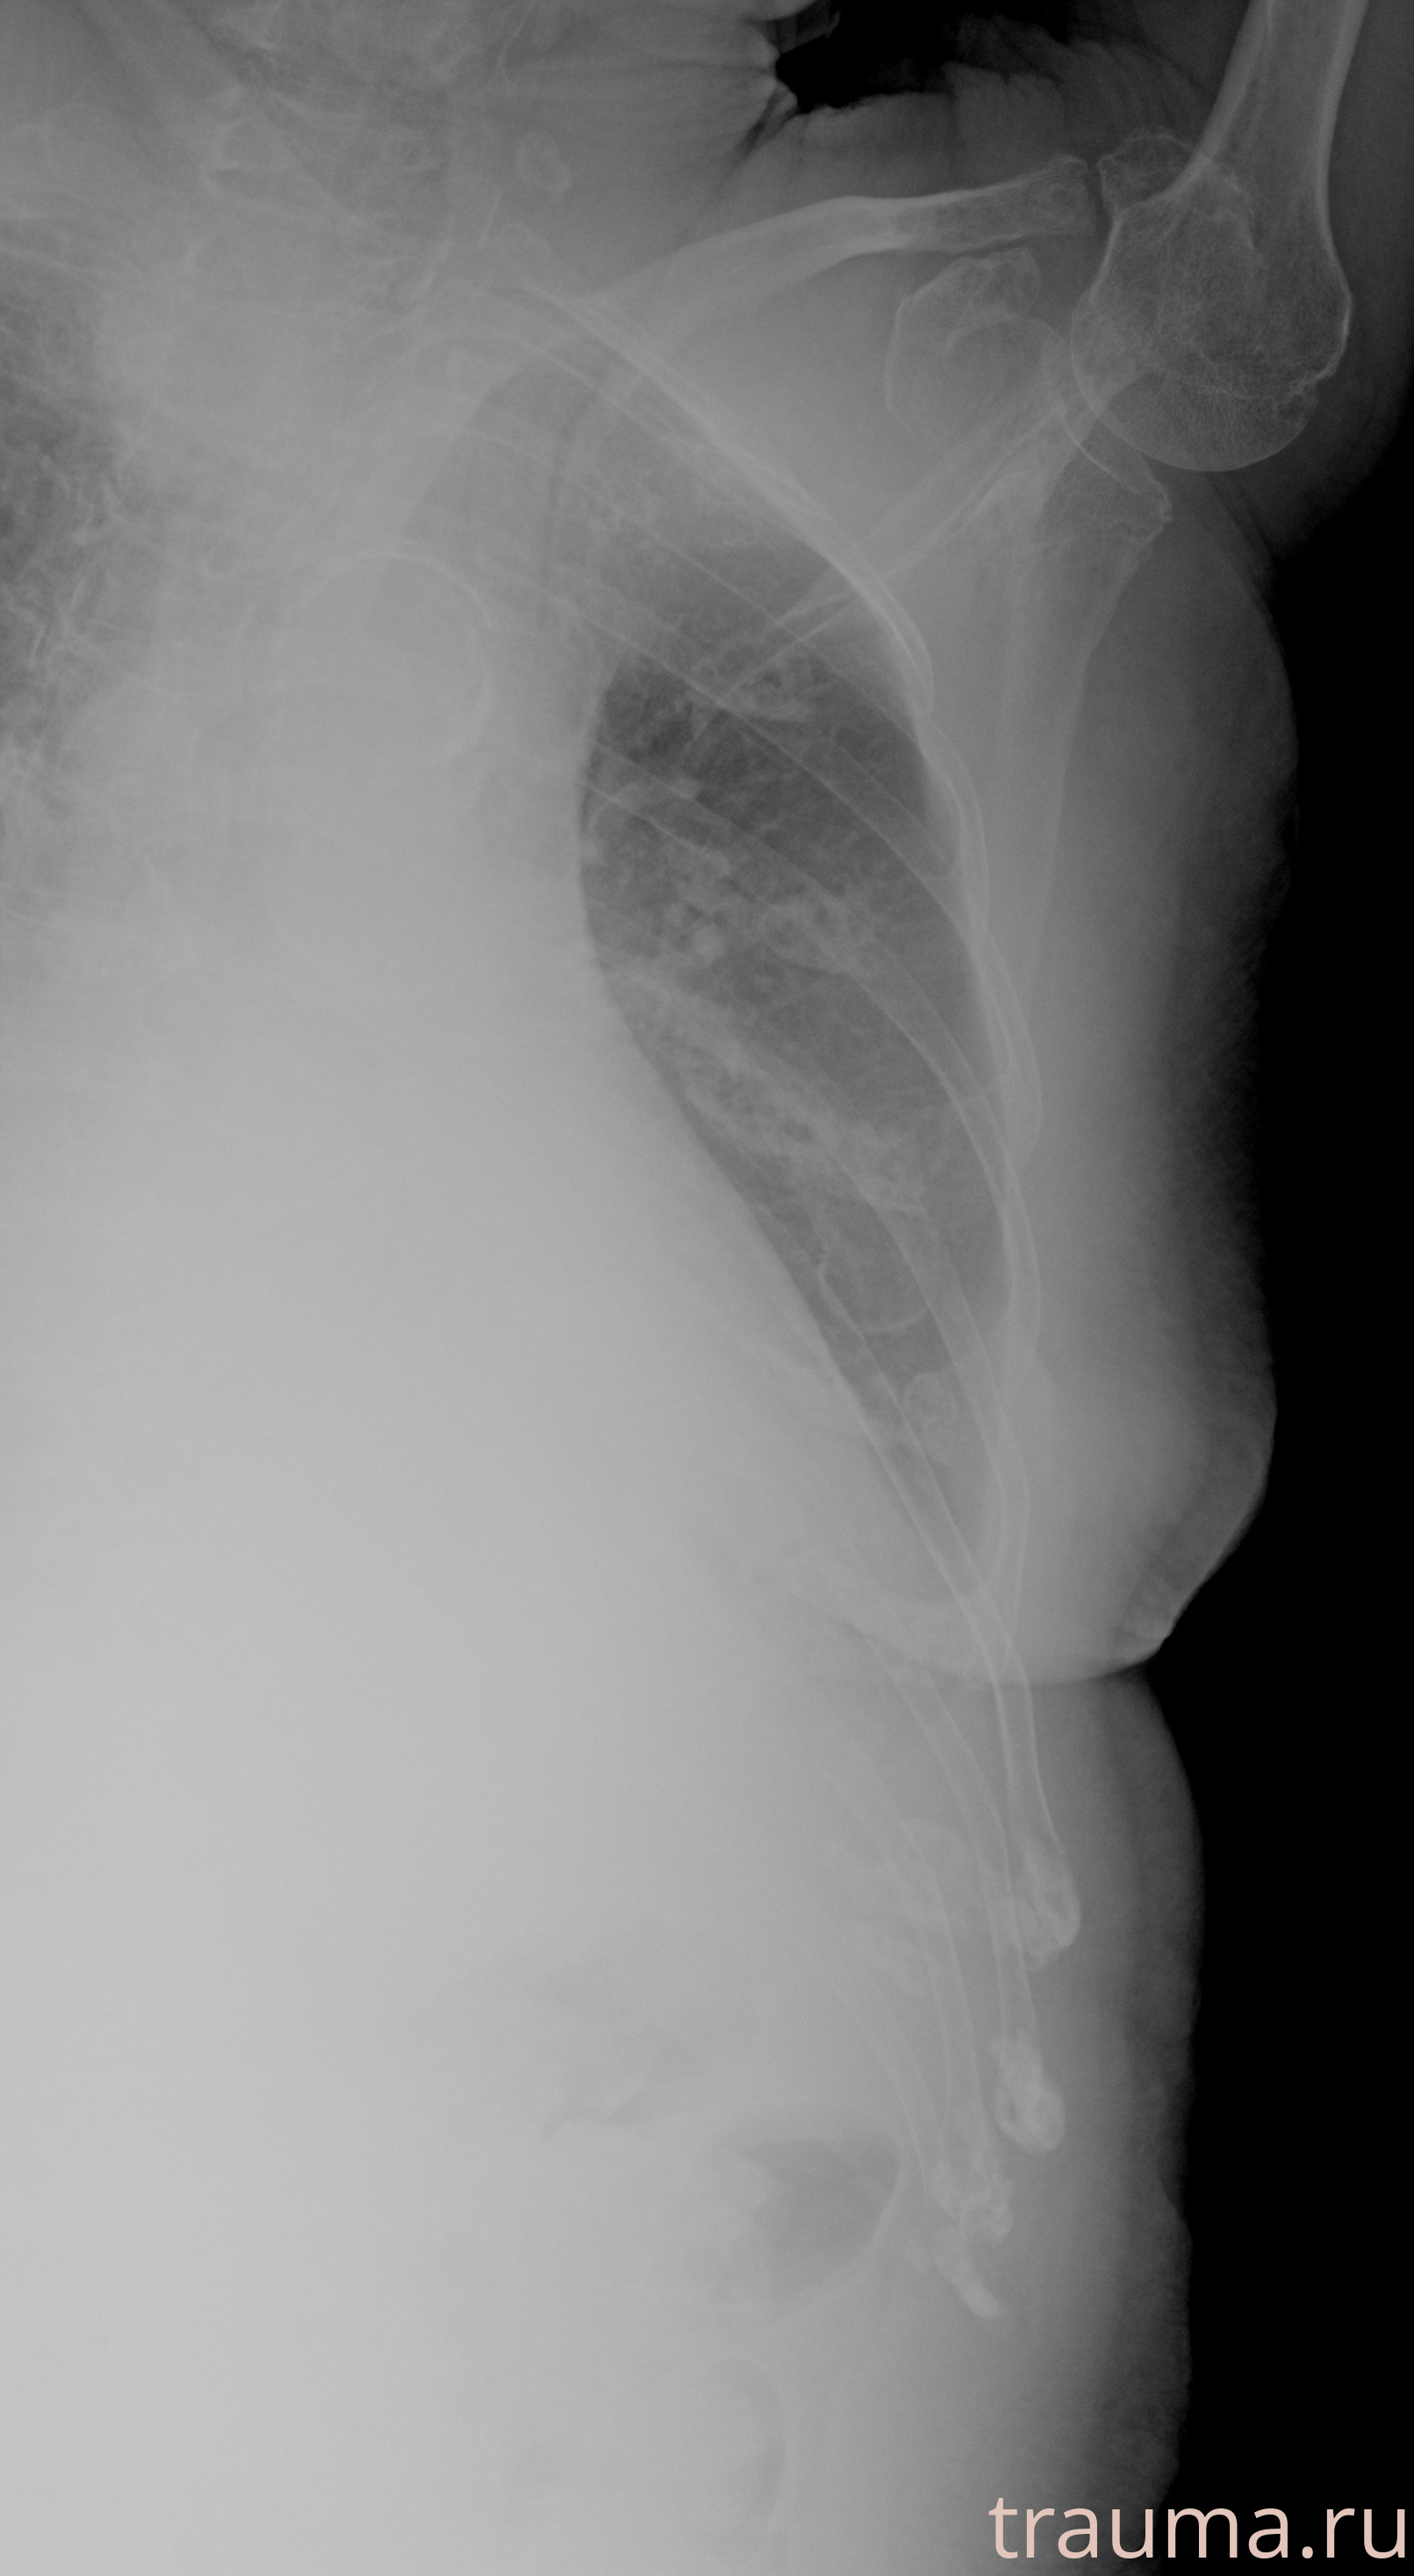

Рентгенограммы

Рентген на дому: по вашему адресу приезжает врач-рентгенолог, травматолог-ортопед с мобильным рентгеновским аппаратом, проводит диагностику травмы или заболевания, делает необходимые рентгенограммы, дает рекомендации по дальнейшему лечению. Получить качественные снимки в домашних условиях возможно благодаря уникальной методике, разработанной МосРентген Центром для института  Склифосовского

при переломе шейки бедра и пневмонии от компании МосРентген Центр - партнера Института имени Склифосовского